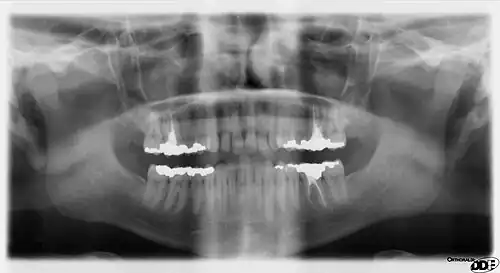

A panoramic radiograph is a panoramic scanning dental X-ray of the upper and lower jaw. It shows a two-dimensional view of a half-circle from ear to ear. Panoramic radiography is a form of focal plane tomography; thus, images of multiple planes are taken to make up the composite panoramic image, where the maxilla and mandible are in the focal trough and the structures that are superficial and deep to the trough are blurred.

Dental panoramic radiography equipment consists of a horizontal rotating arm which holds an X-ray source and a moving film mechanism (carrying a film) arranged at opposed extremities. The patient's skull sits between the X-ray generator and the film. The X-ray source is rectangular collimated beam.[1] Also the height of that beam covers the mandibles and the maxilla regions. The arm moves and its movement may be described as a rotation around an instant center which shifts on a dedicated trajectory.

The manufacturers propose different solutions for moving the arm, trying to maintain constant distance between the teeth to the film and generator. Also those moving solutions try to project the teeth arch as orthogonally as possible. It is impossible to select an ideal movement as the anatomy varies very much from person to person. Finally a compromise is selected by each manufacturer and results in magnification factors which vary strongly along the film (15%-30%). The patient positioning is very critical in regard to both sharpness and distortions.

The collimation of the machine means that, while rotating, the X-rays project only a limited portion of the anatomy onto the film at any given instant but, as the rotation progresses around the skull, a composite picture of the maxillo-facial block is created. While the arm rotates, the film moves in a such way that the projected partial skull image (limited by the beam section) scrolls over it and exposes it entirely. Not all of the overlapping individual images projected on the film have the same magnification because the beam is divergent and the images have differing focus points. Also not all the element images move with the same velocity on the target film as some of them are more distant from and others closer to the instant rotation center. The velocity of the film is controlled in such fashion to fit exactly the velocity of projection of the anatomical elements of the dental arch side which is closest to the film. Therefore, they are recorded sharply while the elements in different places are recorded blurred as they scroll at different velocity.

The dental panoramic image suffers from important distortions because a vertical zoom and a horizontal zoom both vary differently along the image. The vertical and horizontal zooms are determined by the relative position of the recorded element versus film and generator. Features closer to the generator receive more vertical zoom. The horizontal zoom is also dependent on the relative position of the element to the focal path. Features inside the focal path arch receive more horizontal zoom and are blurred; features outside receive less horizontal zoom and are blurred.

The result is an image showing sharply the section along the mandible arch, and blurred elsewhere. For example, the more radio-opaque anatomical region, the cervical vertebrae (neck), shows as a wide and blurred vertical pillar overlapping the front teeth. The path where the anatomical elements are recorded sharply is called "focal path".